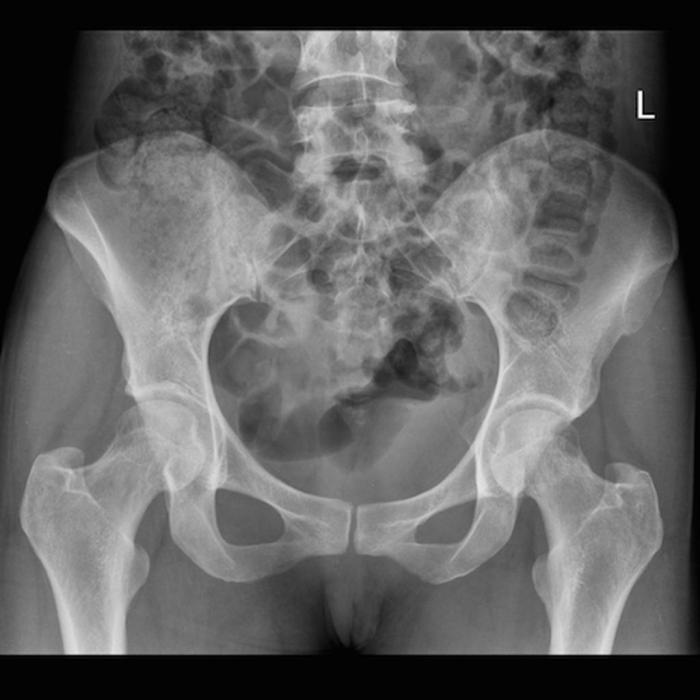

Pelvic XR for the case found here:

Image courtesy of Dr Jeremy Jones, Radiopaedia.org, rID: 28928